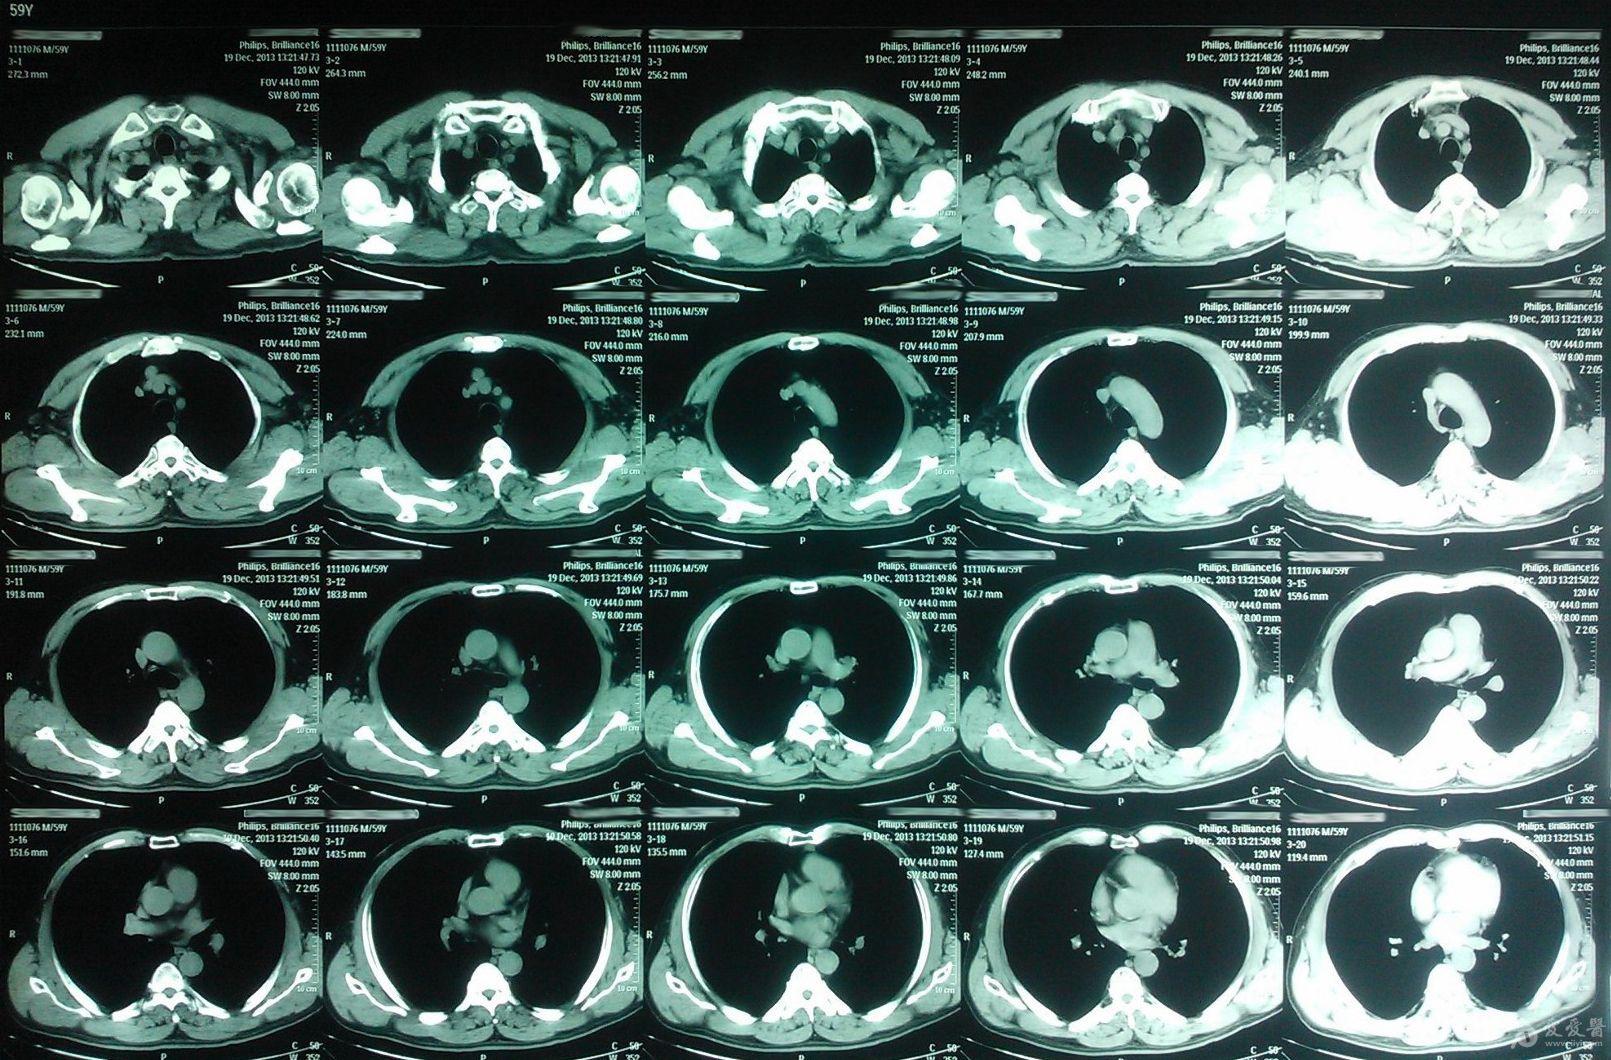

男62岁,右心膈角占位性病变

楼主artest2013-11-24 11:33:10男 62岁,右心膈角占位性病变 ct值约